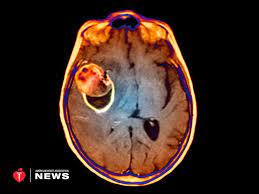

Neurosurgeons make a small opening in the skull and place a titanium clip to prevent blood.

How to prevent brain aneurysm. The two most effective treatments for brain aneurysms today are: Once an aneurysm is found, it is not expected to resolve on its own. Surgically placed platinum wire coils reduce blood flow into the aneurysm;